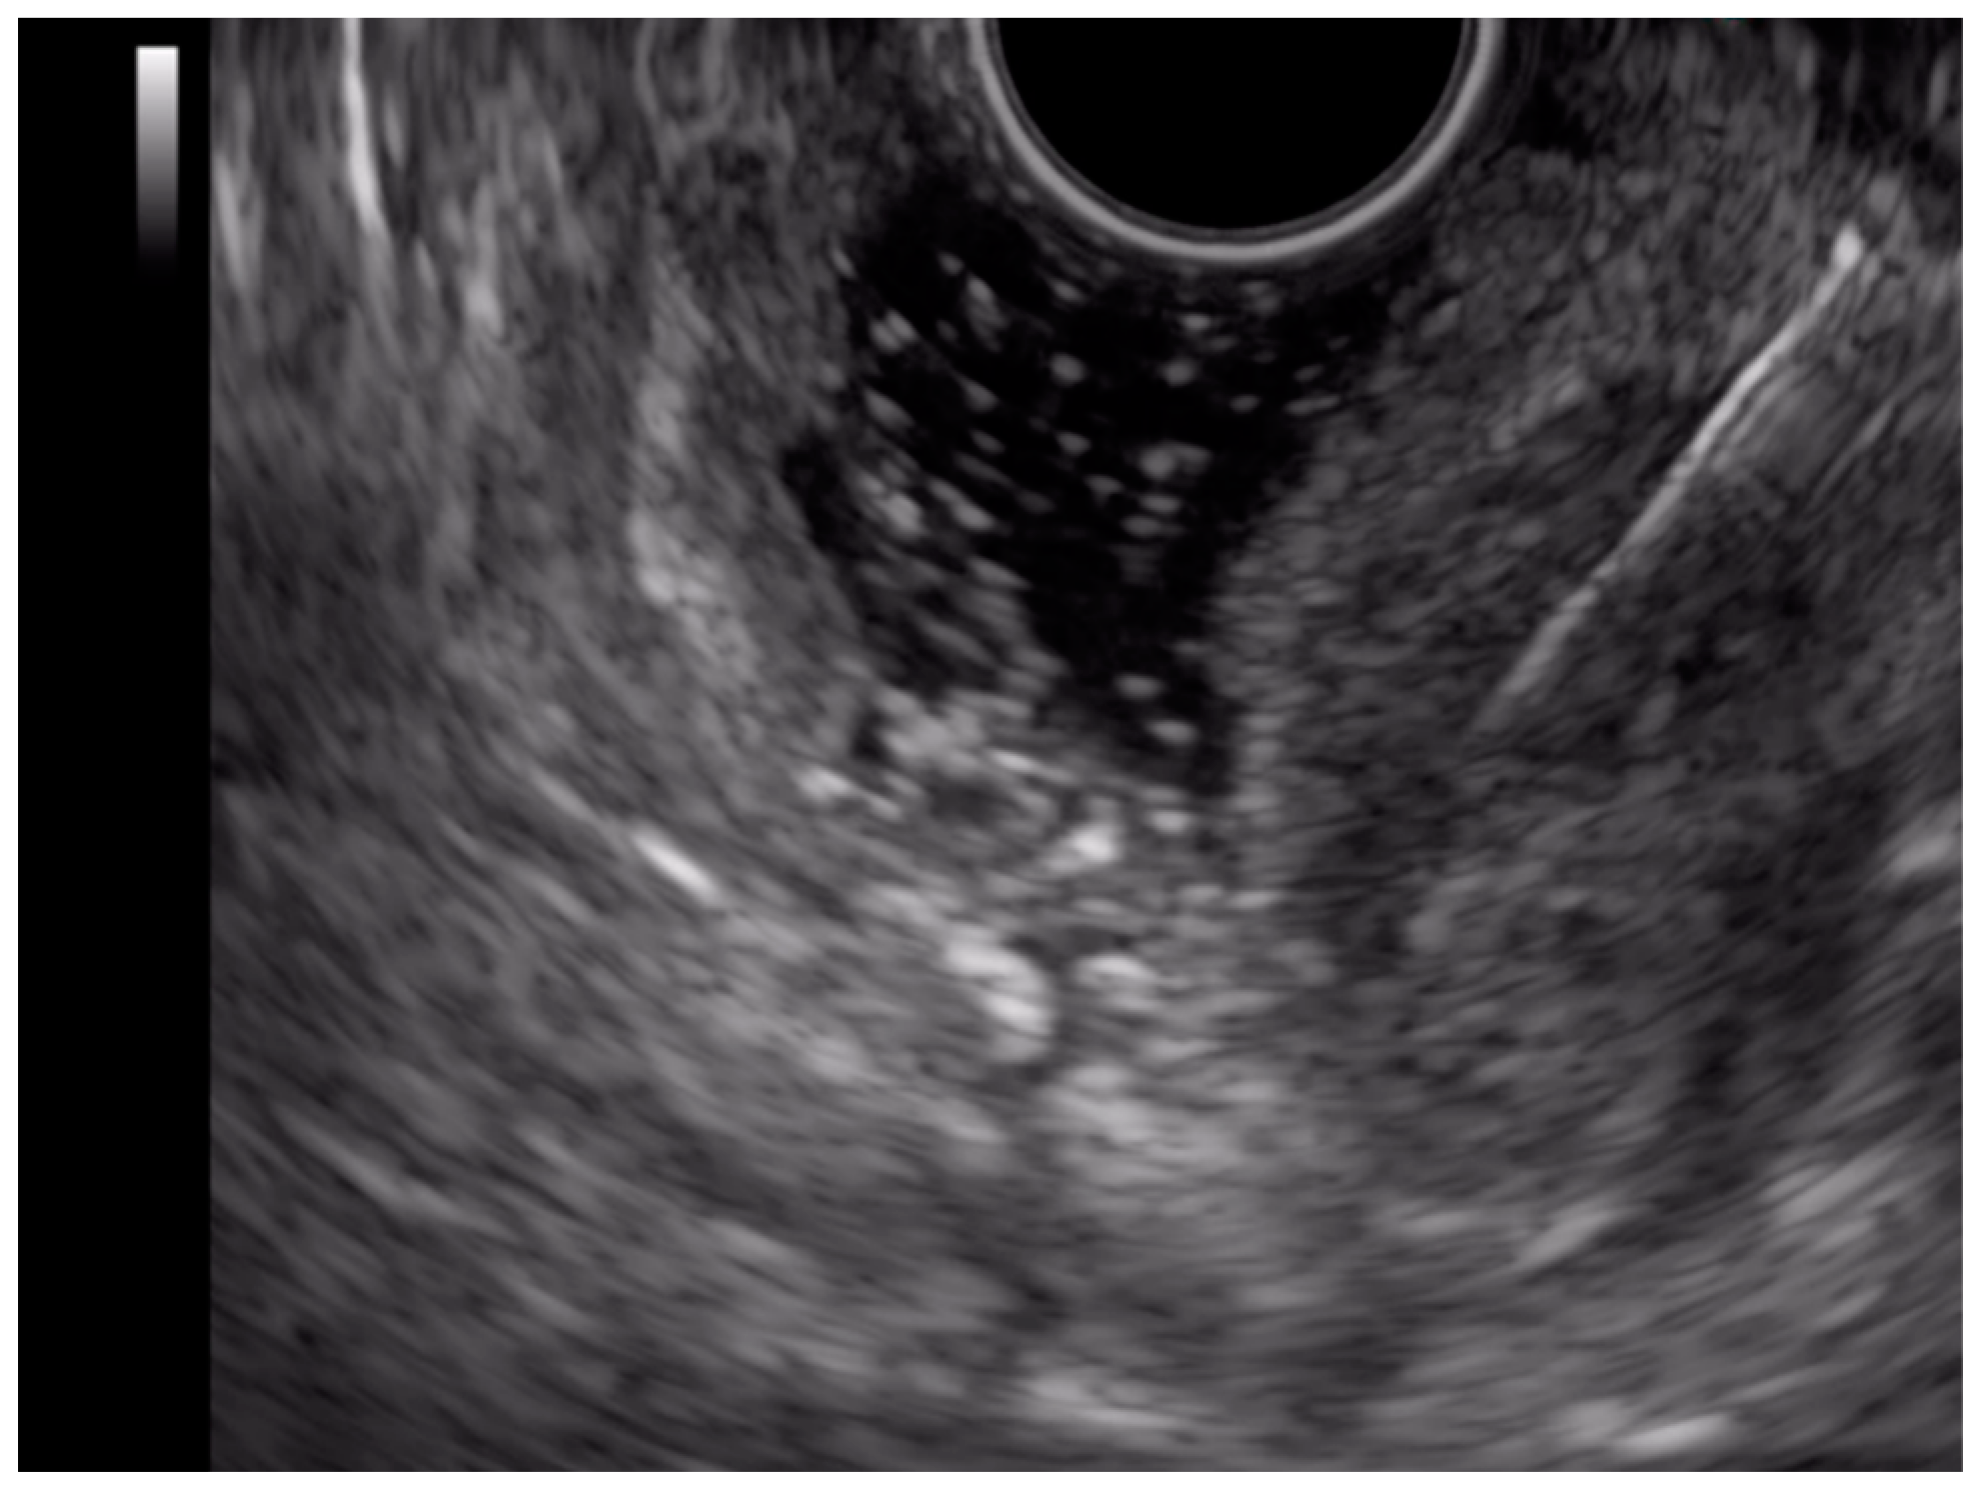

2.3. Endoscopic Ultrasound (EUS)